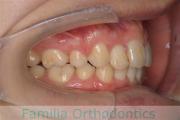

No.23V-069

- 上下顎前突

- 叢生

- 25歳

- 女性

- 上:

- 44

- 下:

- 主な使用装置:

- FEA 022

- 治療にかかった費用:

- 88万円

前歯のでこぼこと口元の突出感を治したいということで来院されました。上下の前歯の突出がある上下顎前突と叢生のケースでした。上下左右から小臼歯を抜歯を抜歯してマルチブラケット法にて治療を行いました。2年強、25回程度の通院が必要でした。

- ≫治療前

- ≫治療後

特に治療前に内側に入っていた上の側切歯の後戻りリスクが大きいケースです。